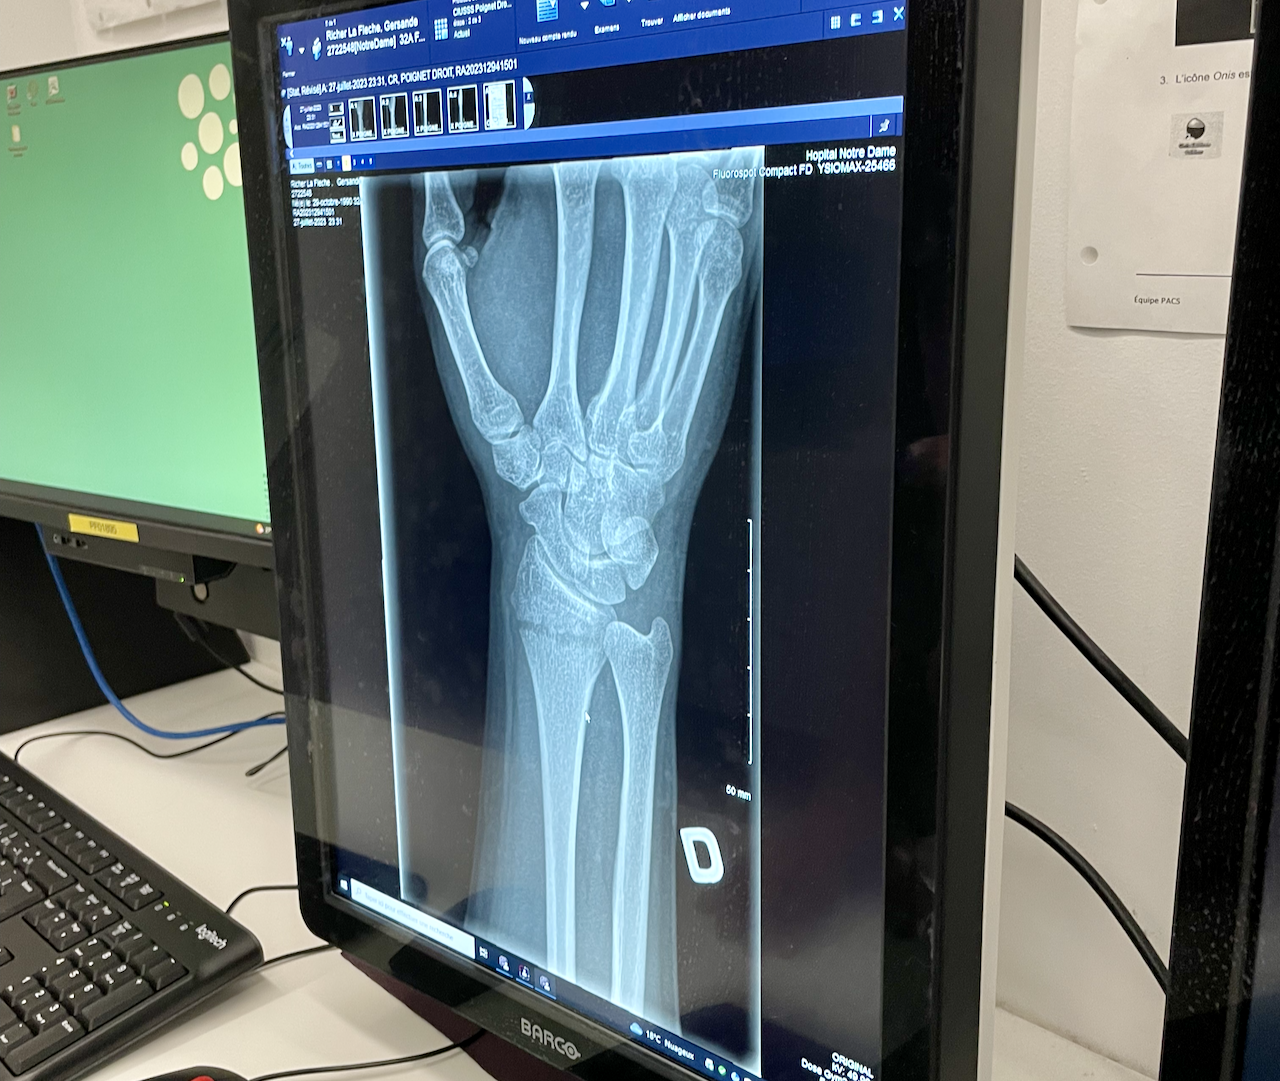

I broke a bone for the very first time on July 27, 2023. The tale of how I was betrayed by gravity and gifted a distal radius fracture is pretty silly, all things considered:

X-rays taken on September 6 2023 show that the bone is looking a lot less broken, but a lateral view shows that it hasn't yet finished putting itself back together yet, as there is still a rather large gap under my wrist.